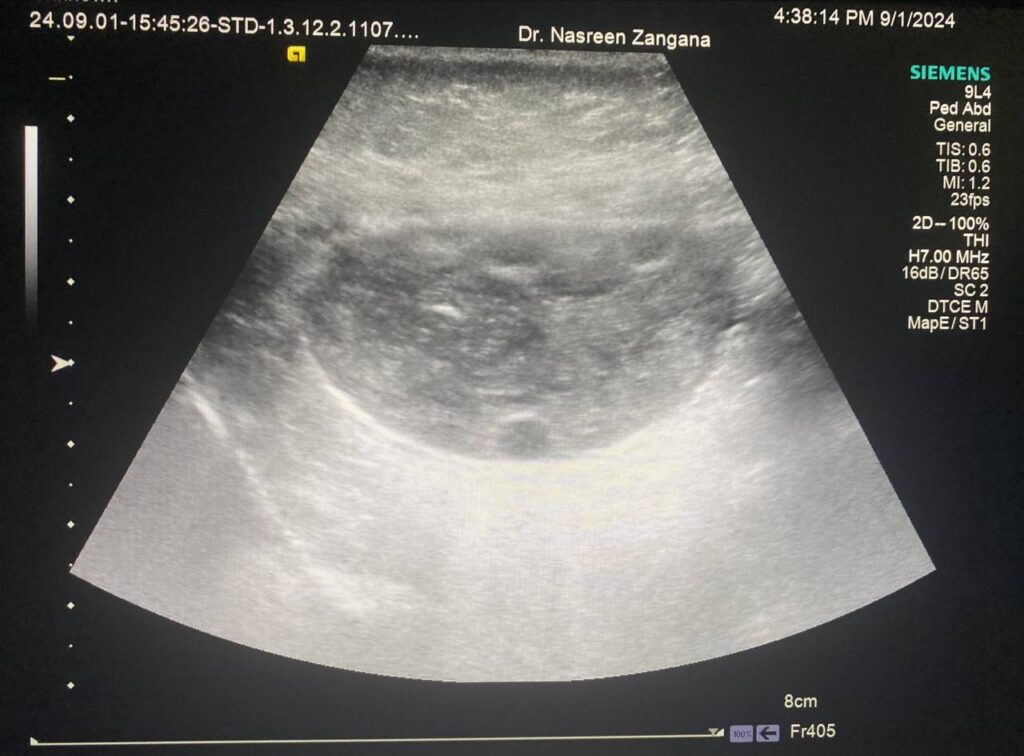

10 years old girl, right ovary enlarge in size with peripheral follicles & little vascularity within, mostly Ovarian Tosrion ?